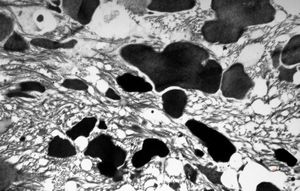

M, 7w. | mitochondrial cardiomyopathy - semithin section(arrows - megamitochondria)

M, 7w. | mitochondrial cardiomyopathy (N - nucleus, M - megamitochondria,R - dilated endoplasmic reticulum)- autopsy sample

M, 7w. | mitochondrial cardiomyopathy … (N … nucleus, F … myofilaments,L … lipid droplets surrounded by megamito